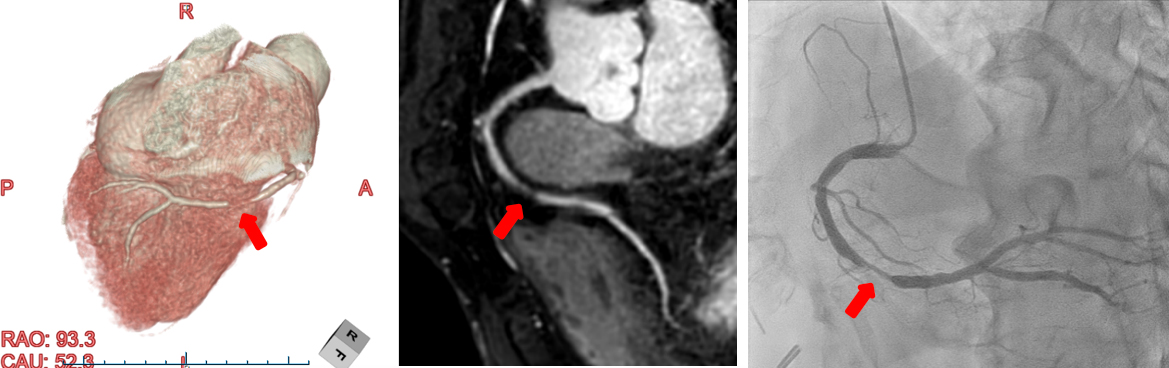

サブトラクション冠動脈CT

これまで、CTでは評価が難しいとされている冠動脈の強い石灰化部位やステント治療部位において、我々が考案した特殊な撮影(test bolus tracking法)および画像処理技術を用いて評価可能な画像を可能な限り提供しています。

Yamaguchi T. Ichikawa K, Takahashi D. et.al. A New Contrast Enhancement Protocol for Subtraction Coronary Computed Tomography Requiring a Short Breath-Holding Time. Academic Radiology Published online: October 17, 2016

SMILIE

さらに、これまでMRIで評価されてきた心筋性状も、我々の考案する画像処理方法(SMILIE:subtraction myocardial image for late iodine enhancement)によって冠動脈と一緒に評価する事が可能となっています。